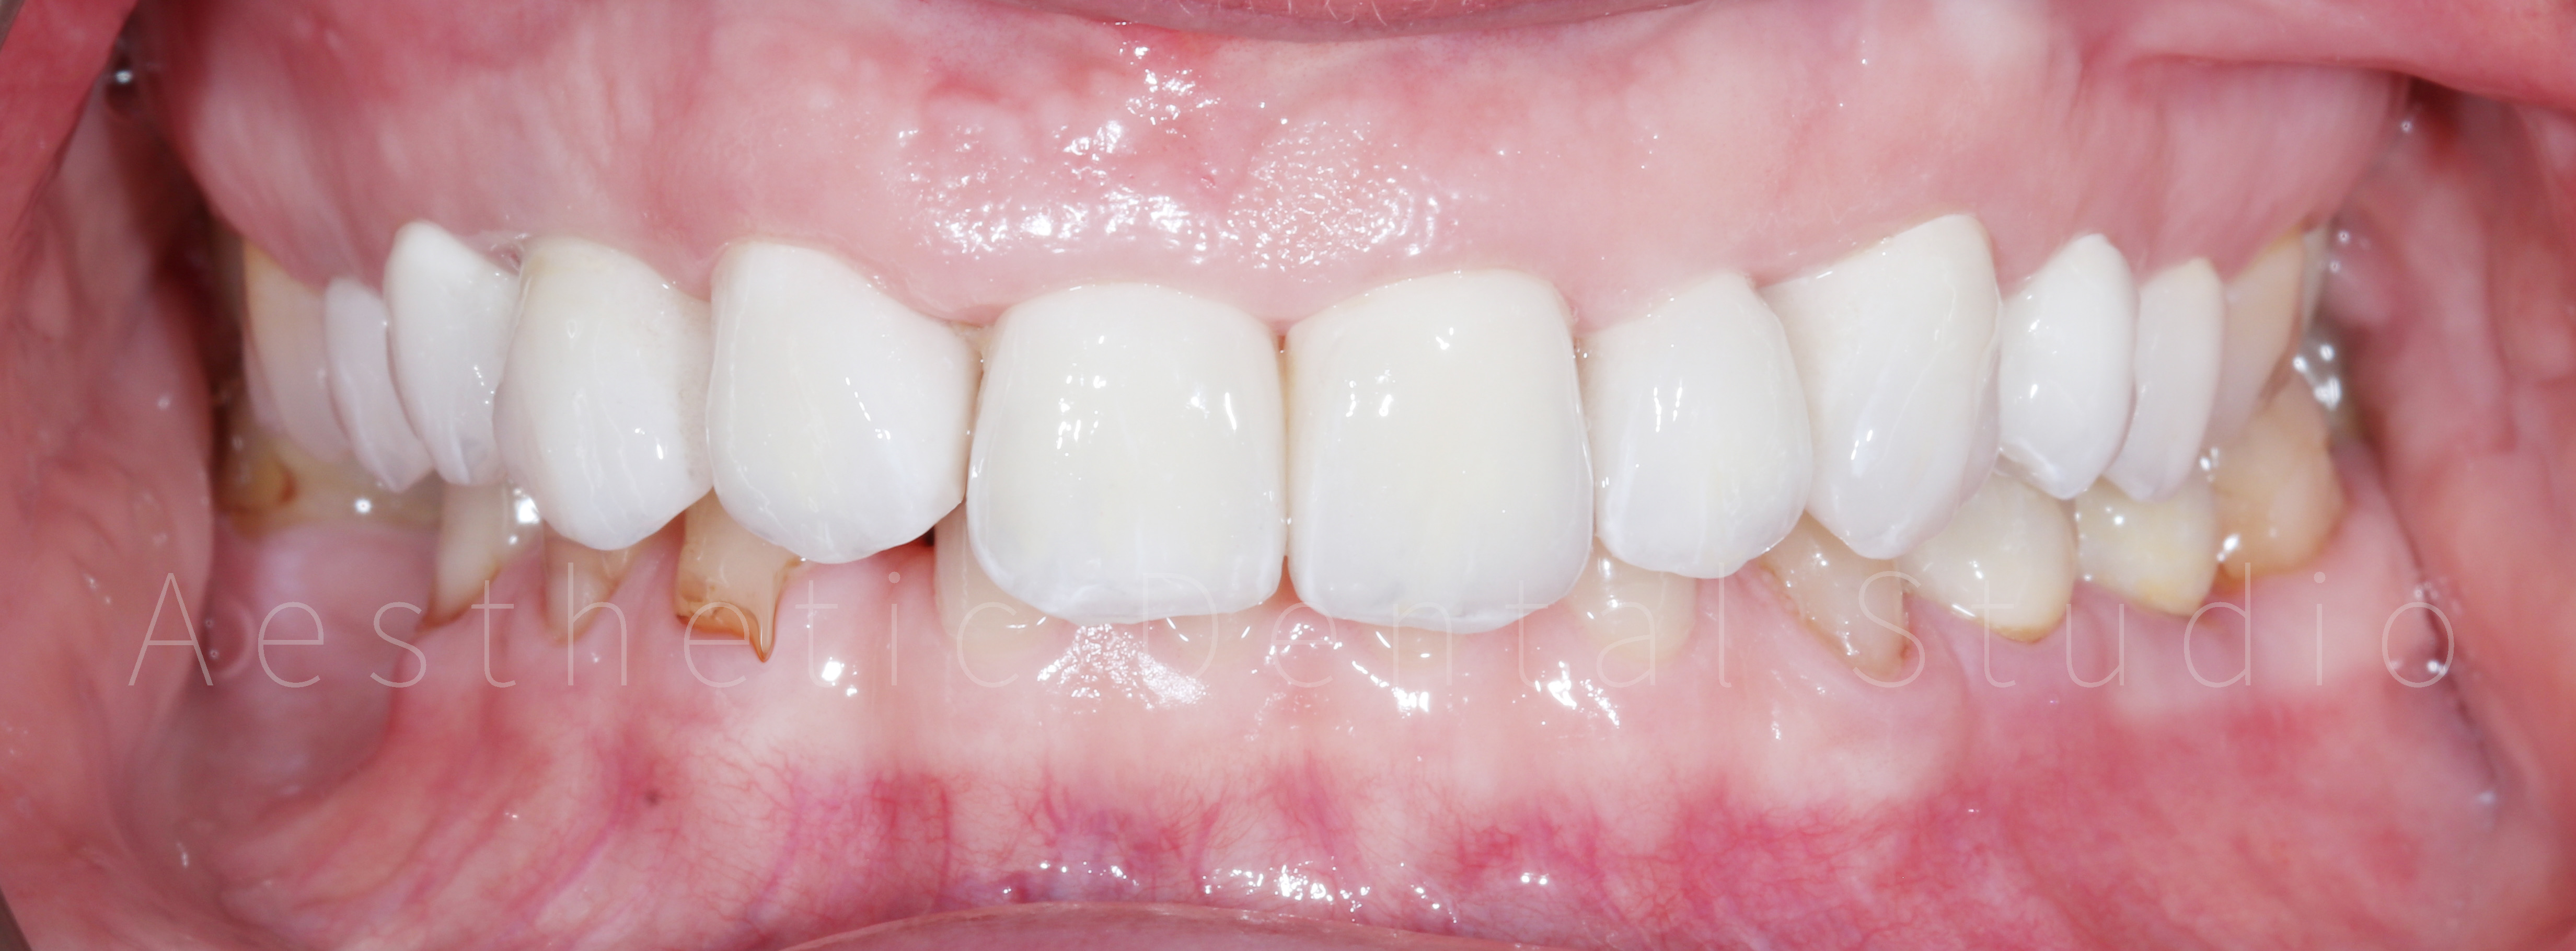

Ακολούθησε η προετοιμασία των δοντιών και η λήψη ψηφιακών αποτυπωμάτων με ενδοστοματικό σαρωτή, τα οποία στάλθηκαν στο συνεργαζόμενο εργαστήριο. Εκεί σχεδιάστηκαν και κατασκευάστηκαν ολοκεραμικές αποκαταστάσεις υψηλής αισθητικής, με απόλυτη ακρίβεια εφαρμογής και χρωματική φυσικότητα. Οι τελικές όψεις και στεφάνες τοποθετήθηκαν στα δόντια της ασθενούς μετά από προσεκτικό έλεγχο αισθητικής, φώνησης και λειτουργίας, επιτυγχάνοντας απόλυτη εναρμόνιση με το πρόσωπο.

Τελικό αποτέλεσμα

Το τελικό χαμόγελο ήταν φυσικό, φωτεινό και αρμονικό, αναδεικνύοντας τα χαρακτηριστικά της ασθενούς, χωρίς υπερβολές. Η θεραπεία ολοκληρώθηκε μέσα σε 10 ημέρες, συνδυάζοντας αισθητική αριστεία, λειτουργική σταθερότητα και άριστο χρονοπρογραμματισμό. Η ασθενής αναχώρησε από την Καλαμάτα με ένα εντελώς ανανεωμένο χαμόγελο, απολαμβάνοντας τη μοναδική εμπειρία ενός αισθητικού ταξιδιού οδοντιατρικής φροντίδας στην Ελλάδα